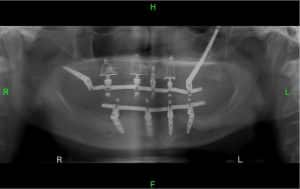

Зубные имплантаты

Специализированные имплантаты для экстремальных случаев отсутствия челюстной кости — скуловые имплантаты

Скуловые имплантаты представляют собой специализированные имплантаты,

предназначенные для использования имплантации зубов в экстремальных случаях отсутствия верхней челюстной кости.

Когда существует недостаток кости, в верхней челюсти нет стабильной точки для закрепления имплантатов.

Скуловые имплантаты длиннее обычных имплантатов,

что позволяет обойти область отсутствия кости в челюсти и прикреплять их непосредственно к кости щеки или,

по профессиональному названию, к скуловой кости, которая и дала имплантатам их название.

Длинный скуловой имплантат при недостатке кости в верхней челюсти